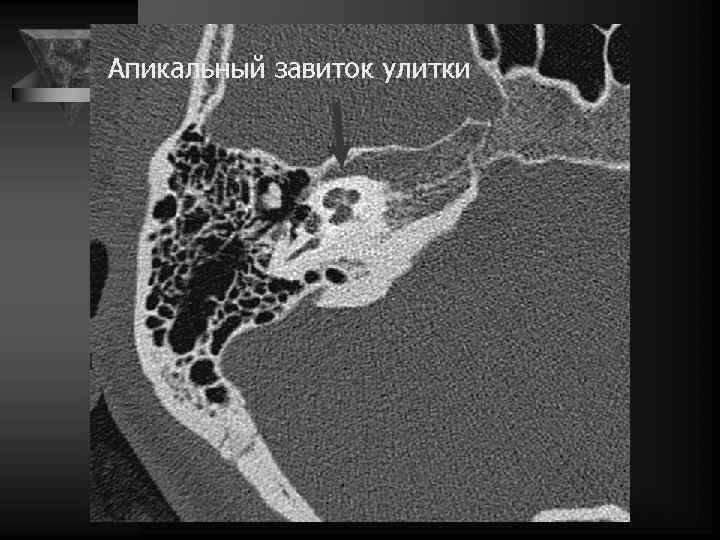

Внутреннее ухо и верхушка пирамиды • Улитка: деминерал-я костной капсулы, спирал-й канал улитки и его просвет, оссификация • Преддверие и полукружные каналы, интактные стенки, оссификация • Внутр. слух. проход: расширение, неровн-ть контура, деструкция кости, стеноз • Канал лицев. нерва до коленч. ганглия. • Водопровод преддв-я и водопр. улитки. • Верхушка пирамиды: губчатая или пневматизирована, наличие секрета, наличие образований